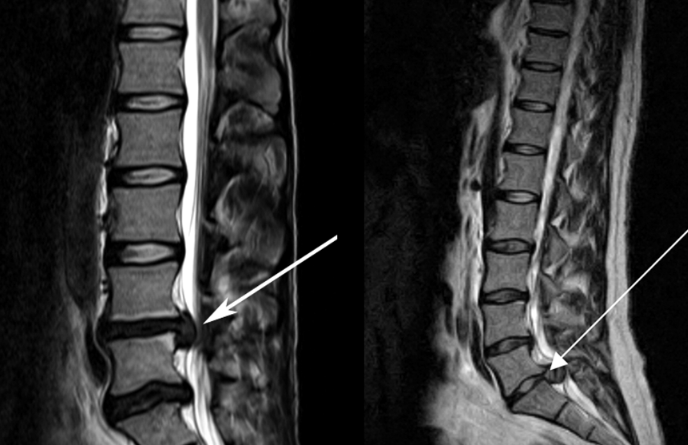

![]() 關(guān)于腰椎間盤突出 ![]() 腰椎間盤突出癥是纖維環(huán)破裂后髓核突出壓迫神經(jīng)根造成以腰腿痛為主要表現(xiàn)的疾病。腰椎間盤退行性改變或外傷所致纖維環(huán)破裂,髓核從破裂處脫出,壓迫腰椎神經(jīng),從而出現(xiàn)腰腿放射性疼痛。 ![]() 病因: 一、退行性變: 目前認(rèn)為,其基本病因是腰椎間盤的退行性變。退行性變是一切生物生、長、衰、亡的客觀規(guī)律,由于腰椎所承擔(dān)的特殊的生理功能,腰椎間盤的退行性變比 其他組織器官要早,而且進(jìn)展相對要快。這個(gè)過程是一個(gè)長期,復(fù)雜的過程。所謂腰椎間盤退行性改變:即由于椎間盤受體重的壓迫,加上腰部又經(jīng)常進(jìn)行彎曲、后伸等活動,易造成椎間盤的擠壓和磨損,尤其是下腰部的椎間盤,從而產(chǎn)生退行性改變。腰椎間盤退行性改變是本病發(fā)生的基礎(chǔ)?!?/p> 二、其他因素: 1、外力作用:在日常生活和工作中,部分人往往存在長期腰部用力不當(dāng)、過度用力姿勢或體位的不正確等情況。例如長期從事彎腰工作的煤礦工人和建筑工人需經(jīng)常彎腰提舉重物。這些長期反復(fù)的外力造成的損傷日積月累地作用于椎間盤,加重了退變的程度。 2、椎間盤自身解剖因素的弱點(diǎn): (1) 椎間盤在成人之后逐漸缺乏血液循環(huán),修復(fù)能力也較差,特別是在退變產(chǎn)生后,修復(fù)能力更加微弱。 (2) 椎間盤后外側(cè)的纖維環(huán)較為薄弱,而后縱韌帶在腰5、骶1平面時(shí)寬度顯著減少,對纖維環(huán)的加強(qiáng)作用明顯減弱。 (3) 腰骶段先天異常:腰骶段畸形可使發(fā)病率增高,這些異常造成椎間隙寬度不等,并常造成關(guān)節(jié)突出,關(guān)節(jié)受到更多的旋轉(zhuǎn)勞損,使纖維環(huán)受到的壓力不一,加速退變。 3、種族、遺傳因素:有色人種發(fā)病率較低,例如印第安人和非洲黑人等發(fā)病率較其他民族明顯要低。 ![]() 2 病理 腰椎間盤突出癥的病理變化過程大致可分為三個(gè)階段: 1、突出前期:髓核因退變和損傷可變成碎塊狀物,或呈瘢痕樣結(jié)締組織,變性的纖維環(huán)可因反復(fù)損傷而變薄變軟或產(chǎn)生裂隙。此期病人可有腰部不適或疼痛,但無放射性下肢痛。也有的人原無病變,可因一次大的暴力引起髓核突出。 2、突出期:外傷或正常的活動使椎間盤壓力增加時(shí),髓核從纖維環(huán)薄弱處或破裂處突出。突出物刺激或壓迫神經(jīng)根即發(fā)生放射性下肢痛,或壓迫馬尾神經(jīng)發(fā)生大小便功能障礙。在老 年患者,可因椎間盤退變,整個(gè)纖維環(huán)變得軟弱松弛,椎間盤可呈彌漫性向周圍膨出。 3、突出晚期:腰椎間盤突出后,病程較長者,椎間盤本身和其他鄰近結(jié)構(gòu)均可發(fā)生各種繼發(fā)性病理改變。 3 誘發(fā)因素 腰椎間盤突出癥的基本因素是椎間盤退變,但某些誘發(fā)因素可致使椎間隙壓力增高,引起髓核突出。此種誘發(fā)因素常與以下因素有關(guān): 1. 年齡因素:腰椎間盤突出癥的好發(fā)年齡在30-50歲,平均手術(shù)年齡在40歲,因此退變可能是其重要因素。 2. 身高與性別:有人認(rèn)為身材過高也會易發(fā)腰突癥,而男性發(fā)病率是女性的5倍?!?/p> 3. 增加腹壓:臨床上有約1/3的病人在發(fā)病前有明確的增加腹壓的因素,如劇烈的咳嗽、噴嚏、屏氣、用力排便等。使腹壓增高,破壞了椎節(jié)與椎管之間的平衡狀態(tài)?!?/p> 4. 不良體位:人在完成各種工作時(shí),需要不斷更換各種體位以緩解腰部壓力,如長期處于某一體位不變,即可導(dǎo)致局部的累積性損傷。特別是長期處于不良姿勢更容易誘發(fā)本病。 5. 職業(yè)因素:重體力勞動者發(fā)病率最高,白領(lǐng)勞動者最低。汽車駕駛員由于長期處于顛簸和振動狀態(tài),椎間盤承受的壓力大且反復(fù)變化,也易誘發(fā)椎間盤突出。 6. 受寒受濕:寒冷或潮濕可引起小血管收縮、肌肉痙攣,使椎間盤的壓力增加,可能造成退變的椎間盤破裂。 ![]() ![]() ![]() ![]() 癥狀: 腰椎間盤突出癥患者最多見的癥狀為疼痛,可表現(xiàn)為腰背痛、坐骨神經(jīng)痛,典型的坐骨神經(jīng)痛表現(xiàn)為由臀部、大腿后側(cè)、小腿外側(cè)至跟部或足背的放射痛。據(jù)臨床統(tǒng)計(jì),約95%的腰突癥患者有不同程度的腰痛,80%的患者有下肢痛。特別是腰痛,不僅是腰椎間盤突出最常見的癥狀,也是最早出現(xiàn)的癥狀之一。 ![]() ![]() ![]() 檢查: 1、X線:腰椎間盤所包括的髓核、纖維環(huán)和軟骨板密度均較低,在X線下并不顯影,因此臨床上腰突癥患者的腰椎X線平片可僅有一些非特異性的變化,甚至無異常變化。因此單純腰椎平片并不能作為有無腰椎間盤突出癥的直接依據(jù),但X線能發(fā)現(xiàn)腰椎的退行性改變和結(jié)構(gòu)異常,對提示椎間盤的退變有重要意義,并且能排除其他的一些腰椎疾患,如腰椎結(jié)核、腫瘤和腰椎滑脫等。典型的腰椎間盤突出癥患者通過病史、體征和X線平片即能作出初步的診斷?!?/p> 2、CT檢查:腰椎的CT可以清楚地顯示椎間盤突出的部位、大小、形態(tài)和神經(jīng)根、硬脊膜受壓的情況,同時(shí)還可顯示黃韌帶肥厚、小關(guān)節(jié)增生、椎管和側(cè)隱窩狹窄等情況。對腰椎間盤突出癥診斷的準(zhǔn)確率達(dá)到80%-92%?!?/p> 3、核磁共振(MRI):核磁共振沒有輻射,可以多方位成像(橫斷面、冠狀面、矢狀面和斜面),對解剖細(xì)節(jié)顯示較好,對組織結(jié)構(gòu)的細(xì)微病理變化更敏感(如骨髓的浸潤),可以排除神經(jīng)和脊柱腫瘤等。對于一些落到椎管的髓核組織也不會遺漏?!?/p> 4、脊髓造影:脊髓造影利用椎管內(nèi)蛛網(wǎng)膜下腔的空隙,注入造影劑后在X線下攝片,顯示椎管內(nèi)部結(jié)構(gòu)。目前常用水溶性造影劑,能較清晰地顯示硬膜腔、馬尾神經(jīng)和神經(jīng)根鞘,對腰椎間盤突出癥的診斷可達(dá)90%左右,主要X線表現(xiàn)為硬膜囊壓迫征象和神經(jīng)根鞘壓迫征象。但由于CT和MRI在臨床的廣泛應(yīng)用,無創(chuàng)傷且診斷率更高,脊髓造影在臨床上的應(yīng)用已經(jīng)大大減少,而且由于它副作用較大,甚至可能造成截癱等嚴(yán)重情況,目前主張慎重選用。 5、肌電圖:肌電圖是對周圍神經(jīng)與肌肉的電生理檢查方法,可用于觀察并記錄肌肉在靜止、主動收縮和支配其的周圍神經(jīng)受刺激時(shí)的電活動,同時(shí)也可用來測量周圍神經(jīng)的傳導(dǎo)速度。在腰椎間盤突出癥上,肌電圖主要通過檢查雙下肢肌肉的興奮性來反映相應(yīng)神經(jīng)根的狀態(tài),并根據(jù)異常電活動的分布范圍來判斷椎間盤突出和神經(jīng)根受壓的節(jié)段。在脊神經(jīng)根和馬尾神經(jīng)受壓的病人,肌電圖陽性率可達(dá)80%-90%,但與CT和MRI相比并不是首選的檢查手段,可用于輔助診斷和判斷神經(jīng)根的受壓情況,同時(shí)也可以用來作為判斷治療后神經(jīng)根恢復(fù)情況的指標(biāo)之一。 ![]() ![]() ![]() 預(yù)防: 腰椎間盤突出癥是在退行性變基礎(chǔ)上積累傷所致,積累傷又會加重椎間盤的退變,因此預(yù)防的重點(diǎn)在于減少積累傷。 日常注意事項(xiàng): 1.平時(shí)要有良好的坐姿,睡眠時(shí)的床不宜太軟。 2.長期伏案工作者需要注意桌、椅高度,定期改變姿勢。 3.職業(yè)工作中需要常彎腰動作者,應(yīng)定時(shí)伸腰、挺胸活動,并使用寬的腰帶。 4.應(yīng)加強(qiáng)腰背肌訓(xùn)練,增加脊柱的內(nèi)在穩(wěn)定性,長期使用腰圍者,尤其需要注意腰背肌鍛煉,以防止失用性肌肉萎縮帶來不良后果。 5.如需彎腰取物,最好采用屈髖、屈膝下蹲方式,減少對腰椎間盤后方的壓力。 ![]() ![]() ![]() 治療: (一)中醫(yī)外敷療法: 腰椎間盤突出可以外貼 腰突正骨膏,其有效成分可透入皮膚產(chǎn)生活血,止痛,化淤,通經(jīng)走絡(luò),開竅透骨,祛風(fēng)散寒等效果,并通過藥物的歸經(jīng)作用而調(diào)理機(jī)體陰陽平衡,滲透于表皮,刺激神經(jīng)末梢,促進(jìn)局部血液微循環(huán),扶正固本、改善體質(zhì),從根本上、全方位針對腰椎疾病病機(jī)特點(diǎn)而發(fā)揮療效,改善病變周圍組織營養(yǎng),起到修復(fù)骨病組織的作用,最終達(dá)到治療目的。 (二)自我治療: 1.腹肌鍛煉: 也就是仰臥起坐。每次做十個(gè),每天三次。(可根據(jù)患者的體質(zhì)來定,不可逞強(qiáng))。 2.交叉扭腰: 兩腳分開與肩寬,腳尖向內(nèi)兩臂伸直,一手在體側(cè),一 手舉過頭頂。如果右手在上,先向左側(cè)后方擺。左側(cè)相反。于此同時(shí)腰部也隨之扭動,左右各100次。 3.抱膝觸胸: 處于仰臥位,雙膝屈曲,手抱住膝部,使盡量靠近胸部,然后放下,一上一下為一個(gè)動作,可持續(xù)30個(gè)。 4.腰背肌鍛煉: 處于平臥,雙膝彎曲放在床上,然后用力將臀部抬起,離開床面10厘米。這時(shí)您會感覺到腰背部在用力,堅(jiān)持5秒鐘,反復(fù)10下。 ![]() (三)非手術(shù)治療: 非手術(shù)療法是治療腰椎間盤突出癥的基本療法,約80%以上的患者經(jīng)保守治療均可得到緩解和痊愈。其主要療法有: 1.日常家庭治療:早期腰椎間盤突出癥,癥狀輕微,不需要做特殊的治療。第一,注意臥床休息,避免腰椎受外力壓迫,第二,應(yīng)用其他方法積極鍛煉腰部肌肉力量。 2.牽引治療; 3.推拿按摩治療; 4.物理治療; 5.消炎鎮(zhèn)痛藥物; 6.減輕神經(jīng)根水腫藥物。 (四)推拿治療: 1.解除腰臀部肌肉痙攣 2.拉寬椎間隙,降低盤間壓力 3.增加椎間盤外壓力 4.調(diào)整后關(guān)節(jié),松解粘連 5.促使受損傷的神經(jīng)根恢復(fù)功能 (五)微創(chuàng)治療: 微創(chuàng)治療方法的目的是消除腰椎間盤突出的髓核以解除對神經(jīng)的壓迫。微創(chuàng)治療技術(shù)采用可視設(shè)備,創(chuàng)口不足一厘米有些甚至不足一毫米。消融或摘除髓核,從根本上解除致病因素,因而能夠取得很好的效果。 (六)手術(shù)治療: 腰椎間盤突出癥的手術(shù)原則是嚴(yán)格無菌操作,盡量保留不必去除的骨結(jié)構(gòu)和軟組織結(jié)構(gòu),以最小的創(chuàng)傷達(dá)到足夠的顯露,仔細(xì)徹底地去除病變組織,達(dá)到治療目的。 ![]() ![]() 綠柏相關(guān)產(chǎn)品: ![]() 懸吊訓(xùn)練療法是康復(fù)醫(yī)學(xué)中以持久改善肌肉骨骼疾病為目的的,應(yīng)用主動治療和訓(xùn)練的一個(gè)總的概念整合,是一種運(yùn)動感覺的綜合訓(xùn)練系統(tǒng),包括診斷與治療兩大系統(tǒng)。 產(chǎn)品特點(diǎn): 1.電腦軟件管理系統(tǒng),涵蓋患者信息管理、評估、訓(xùn)練、量表、報(bào)告、視頻教學(xué)六大模塊,輕松實(shí)現(xiàn)評估與訓(xùn)練一體化管理; 2.多點(diǎn)多軸設(shè)計(jì),滿足不同治療方案設(shè)計(jì); 3.懸吊工作站及各個(gè)懸吊點(diǎn),均能實(shí)現(xiàn)任意位置移動,一鍵解鎖,省時(shí)省力; 4.實(shí)時(shí)力反饋,精準(zhǔn)量化弱鏈測試及懸吊治療全過程,給治療師及患者最直觀的效果呈現(xiàn); 5.智能神經(jīng)肌肉促通裝置,可根據(jù)評估結(jié)果設(shè)置治療模式、頻率、時(shí)間等相關(guān)參數(shù),讓懸吊康復(fù)更加高效有針對性; 6.外觀高端大氣,結(jié)構(gòu)穩(wěn)固,給患者安全保障,增加治療信心。 ![]() |